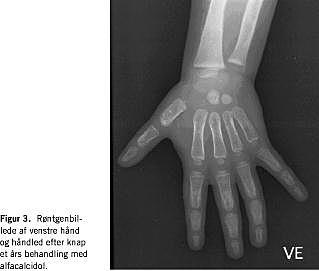

Behandlingen ændredes til 1 mg alfacalcidol. Herefter steg S-calcium-ion og total S-calcium, S-basisk fosfatase og S-PTH faldt (Tabel 1). Efter syv måneder var S-calcium og D-vitamin-stofskiftet normaliseret. Efter tre måneder var der radiologiske tegn på opheling (Figur 2), og efter knap et års behandling var der yderligere opheling af de påviste rakitisforandringer (Figur 3). Patienten og forældrene blev undersøgt for CYP27B1-genet (GeneDx lab. USA). Patienten var homozygot for en 7 bp-duplikation i exon 8 af CYP27B1-genet. Begge forældre var heterozygote for mutationen, havde normalt niveau af S-calcium, S-fosfat og P-1,25 dihydroxy-D-vitamin.

Knogleforandringerne blev ophelet ved behandling med fysiologiske doser af alfacalcidol, en aktiveret D-vitamin-metabolit. Behandlingen er livslang. Det tilstræbes at holde S-calcium på et niveau, der kan holde S-PTH inden for referenceområdet. Er S-calcium for højt, øges risikoen for nefrokalcinosis [5].